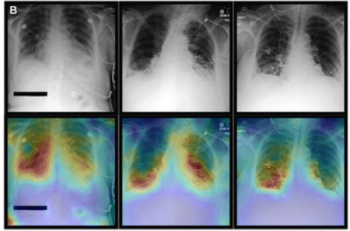

An emerging deep learning algorithm can reportedly triage 40 percent of no-change X-rays while providing 88 to 90 percent accuracy for detecting changes with X-rays obtained in the emergency department and intensive care unit at a tertiary referral hospital, according to recently published research.

Integrating clinical data parameters along with chest X-ray findings, the multimodal artificial intelligence (AI) model outperformed the use of clinical parameters only and chest X-rays only for various conditions ranging from congestive heart failure and chronic kidney disease to hypertension and pneumonia.

In a multicenter study examining four commercially available artificial intelligence (AI) software products for chest X-rays in over 2,000 patients, researchers found sensitivity rates ranging between 33 to 61 percent for vague airspace disease and 9 to 94 percent for small pneumothorax and pleural effusion.